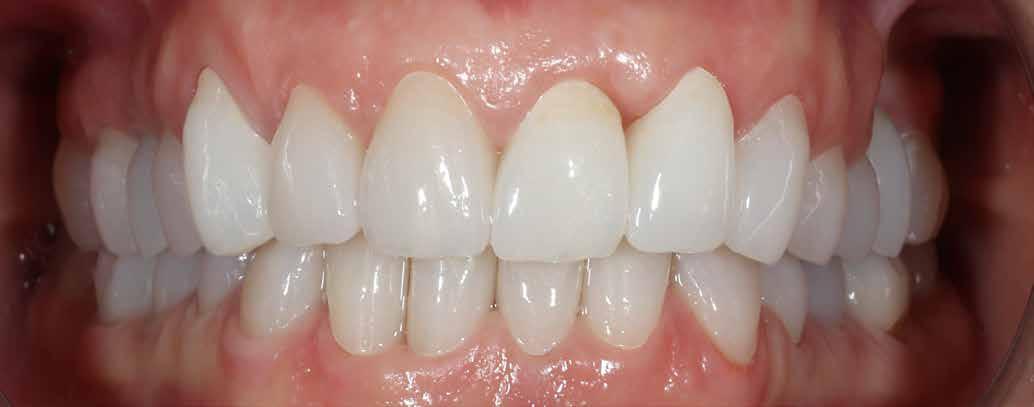

1077 Budapest, Izabella u. 10. Tel.: 06-1-223-3999, info: 06-30/944-1441 www.dentaldiszkont.hu

eszközök és anyagok a legnagyobb választékban, a legkedvezőbb áron. Raktárról azonnal szállítunk. Viszonteladóknak nagy kedvezmények.

Turn static files into dynamic content formats.

Create a flipbook

Issuu converts static files into: digital portfolios, online yearbooks, online catalogs, digital photo albums and more. Sign up and create your flipbook.